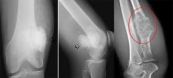

Bệnh Paget ở xương là chứng rối loạn bất thường trong quá trình hình thành và xây dựng cấu trúc xương. Bất kỳ phần xương nào cũng có thể bị ảnh hưởng bởi bệnh Paget. Vậy bệnh lý này có nguy hiểm không? Phương pháp điều trị nào là cần thiết? Tham khảo bài viết dưới đây để hiểu rõ hơn nhé!